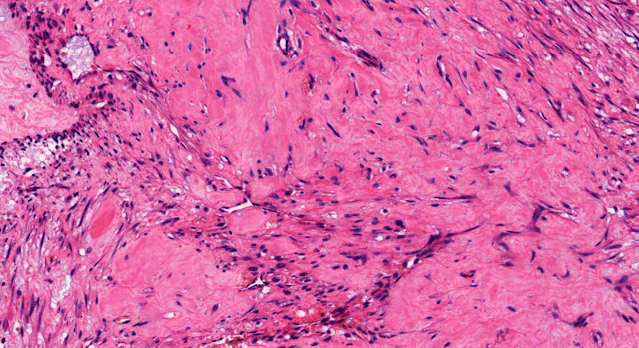

Dermatopathology Case 231 Get link Facebook X Pinterest Email Other Apps June 14, 2022 A rapidly growing nodule on the left forearm of a 35 year old male. Answer Get link Facebook X Pinterest Email Other Apps Comments